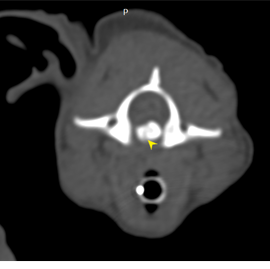

• 臘腸狗狗好發的椎間盤疾病 IVDD 第四級 脊椎外科手術 電腦斷層

臘腸狗狗好發的椎間盤疾病 IVDD 第四級 脊椎外科手術 電腦斷層

• 臘腸狗狗 椎間盤疾病 ivdd

臘腸狗狗 椎間盤疾病 ivdd